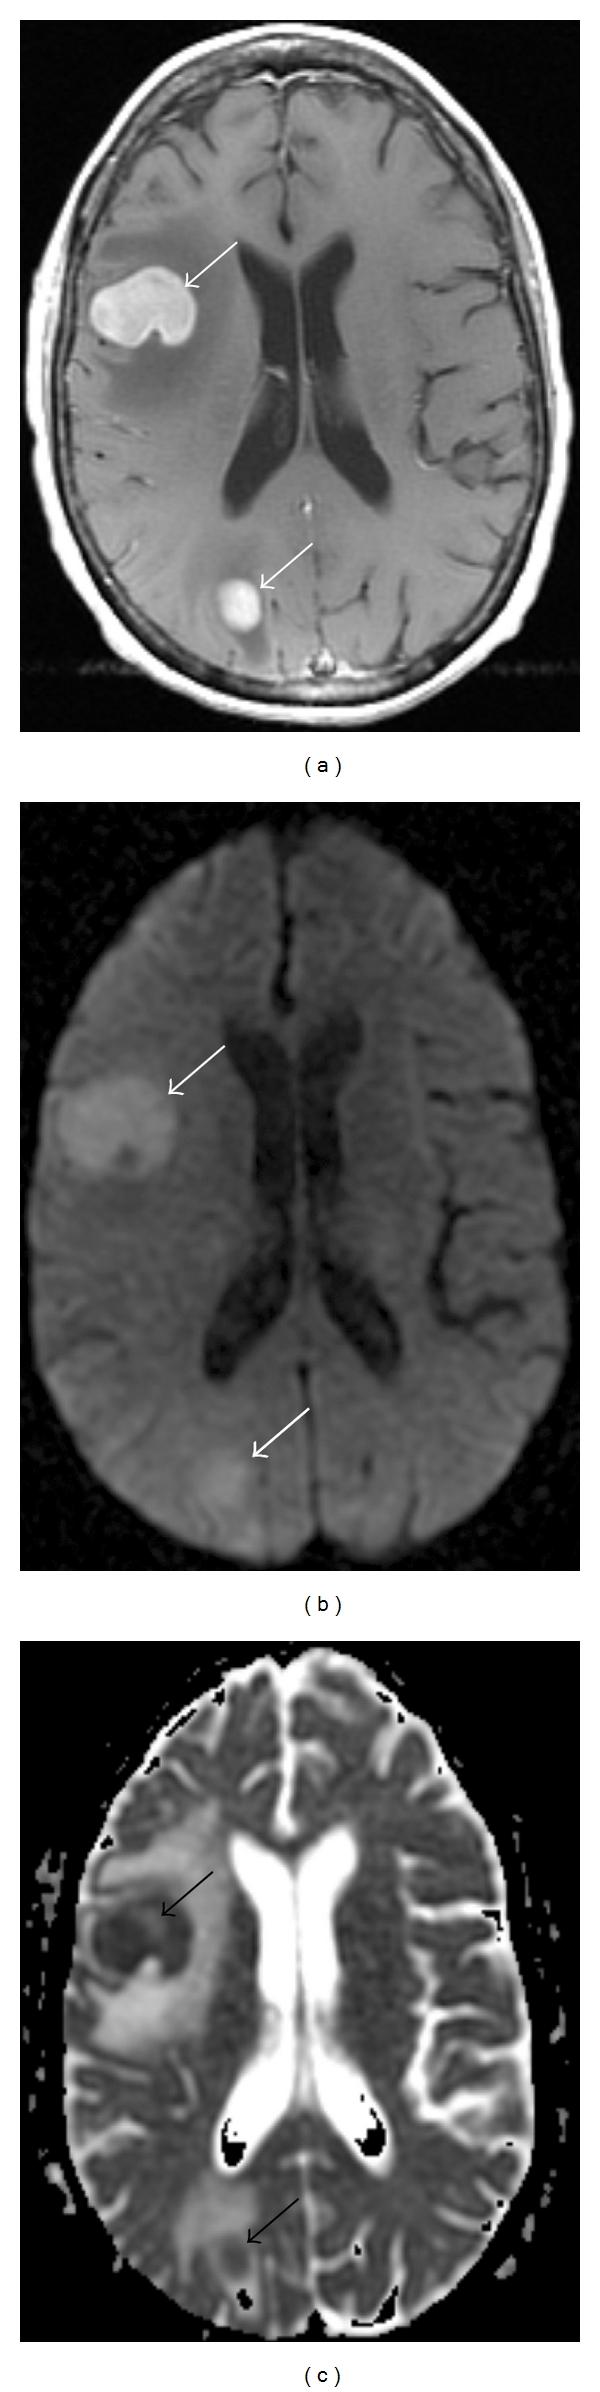

Diffusion MR Imaging of the Brain in Patients with Cancer.

Over the last several years, there has been significant advancement in the molecular characterization of intracranial diseases, particularly cerebral neoplasms. While nuclear medicine technology, including PET/CT, has been at the foreground of exploration, new MR imaging techniques, specifically diffusion-weighted and diffusion tensor imaging, have shown interesting applications towards advancing our understanding of cancer involving the brain. In this paper, we review the fundamentals and basic physics of these techniques, and their applications to patient care for both general diagnostic use and in answering specific questions in selection of patients in terms of expected response to treatment.

在过去几年中,颅内疾病,尤其是脑肿瘤的分子特征研究取得了重大进展。虽然包括PET/CT在内的核医学技术一直处于探索前沿,但新的磁共振成像技术,特别是扩散加权成像和扩散张量成像,在推进我们对脑部癌症的理解方面显示出了有趣的应用。在本文中,我们回顾了这些技术的基本原理和基础物理学,以及它们在患者护理中的应用,包括一般诊断用途以及在回答关于患者对治疗预期反应的特定选择问题方面的应用。